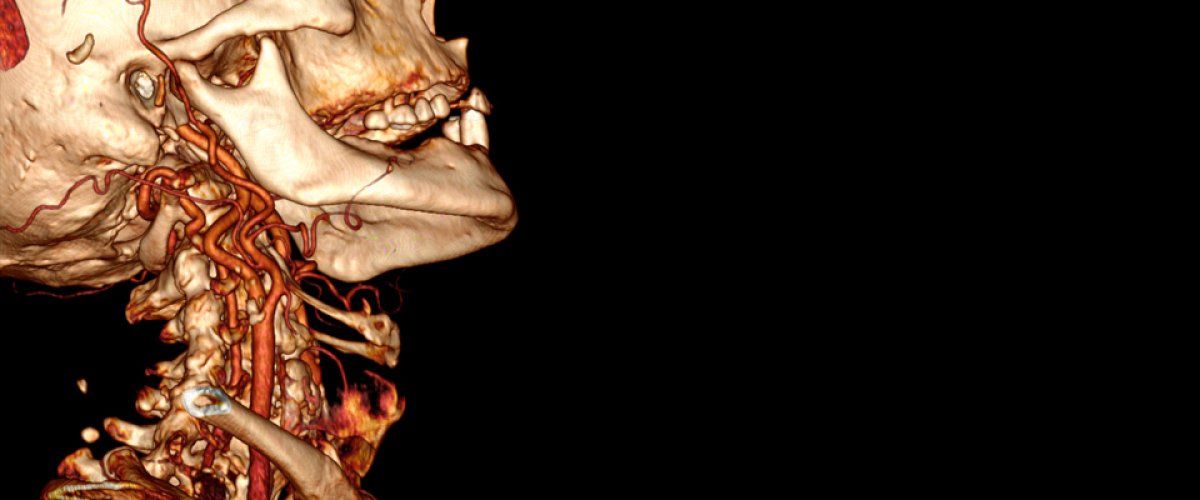

Dr. Patrick M. Tamim is certified vascular surgery. Trust in his expertise to help restore you back to health.

Our office can provide you with services that address your vascular needs. We will tailor your diagnostic testing, surgeries and medications to suit your specific needs. Rest easy knowing that we want what is best for you and your long- term health goals, and will work with you to help you reach those goals. Contact Patrick M. Tamim M.D. today for more information.